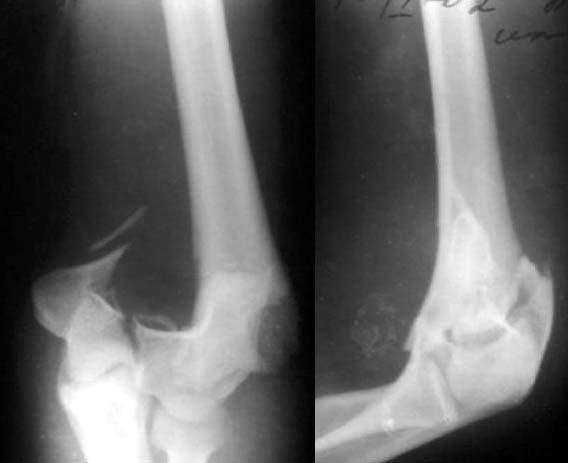

Все же открываться мы не стали. Результаты в приложении. Фронтальный снимок переделаю и пришлю еще раз. Мнения?

А.В.Владзимирский

Кликните для загрузки файла k5.jpg